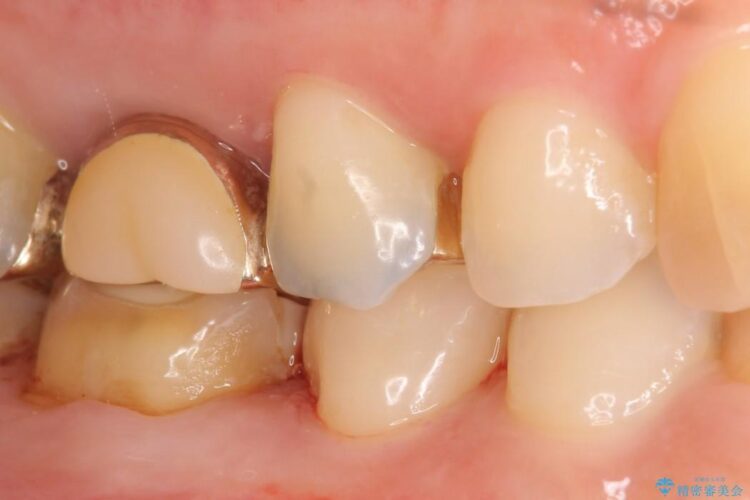

ぱっと見ただけでは特に問題ないように見えますが、レントゲンをよく確認すると詰め物と歯の間に隙間がはっきりと確認ができます。

適合不良であるインレーを放置するリスクを患者様へ説明してご納得いただいた上で、オールセラミックインレーで治療を行うこととしました。